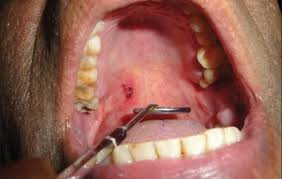

Medikamentenverblisterung von omnicell nutzen um kundenbindung langfristig zu steigern. Most oral blood blisters develop following trauma to the mouth, such as biting your cheek, burning your mouth with hot food, or puncturing soft tissue with sharp food, like a chip. In some cases, you may bite yourself as you talk or chew food. Oral herpes this condition causes blood blisters to form on the inner cheek, gums, tongue and/or the roof of the mouth. They are soft and can break open easily.

If it is a blood blister, it will heal on its own. It is caused by the herpes simplex virus 1 and symptoms, like pain, a burning sensation, fatigue and fever, will be felt. Several different things can cause blisters inside the mouth: The disorder is harmless and the ruptured blisters typically heal within several days. Blood blisters that occur on the roof of your mouth, tongue, or cheek are red in color and filled with blood and other fluids. They are soft and can. The common causes of petechiae are: Unless you have an exact cause and effect mapped out and know the precise event that caused it, see a doctor.

It is a fairly common, sudden onset and benign blood blistering oral (mouth) disorder. Mouth blisters are sores on the lips, cheeks, tongue, or areas inside or around the mouth. Abh is a benign disorder of unknown pathogenesis that primarily affects elderly patients. These blood blisters in mouth burst quickly and heal without much treatment. Blood blisters are a common, minor skin condition. The disorder is harmless and the ruptured blisters typically heal within several days. Blood that escapes from these vessels collects together and forms a blister in your mouth. Oral nevi are usually slightly raised. What causes blisters in the mouth? Gentle rubbing usually lead to the formation of painless blood blister inside cheek. They can appear reddish or purplish in color and are usually big enough to be felt with the tongue. Blood blisters in the cheek are a problem that many people face. Oral herpes this condition causes blood blisters to form on the inner cheek, gums, tongue and/or the roof of the mouth.

It is characterized by small blood blisters that form and pop on the soft palate, which includes the roof of the mouth and inner cheek, within the course of a day. Entdecken sie unser umfangreiches sortiment von standardblister. Angina bullosa hemorrhagica is when a blood blister suddenly appears on the inner side of your cheek or tongue (1). They form due to rupturing of the blood vessels found below epithelial tissues in the mouth. It mainly affects people over 45 years and both males and females are equally affected. No one knows what causes these small, painful blisters inside your mouth. What causes blood blisters in the mouth or cheek? Blood blister found in the mouth and cheek are more worrisome than those on the feet or fingers.

Newly formed blisters are likely to cause pain and itching sensation. It is caused by the herpes simplex virus 1 and symptoms, like pain, a burning sensation, fatigue and fever, will be felt. Accidental biting or scalding of the. Blood that escapes from these vessels collects together and forms a blister in your mouth. Several different things can cause blisters inside the mouth: These spots are usually flat and appear on arms, stomach, legs, and buttocks. A mouth blister is a sore on the lips, cheeks, tongue, or other soft areas inside or around the mouth. A blood blister inside the cheek can make chewing hazardous and is vulnerable to partial puncture and subsequent invasion by the normal bacteria contained within the mouth.